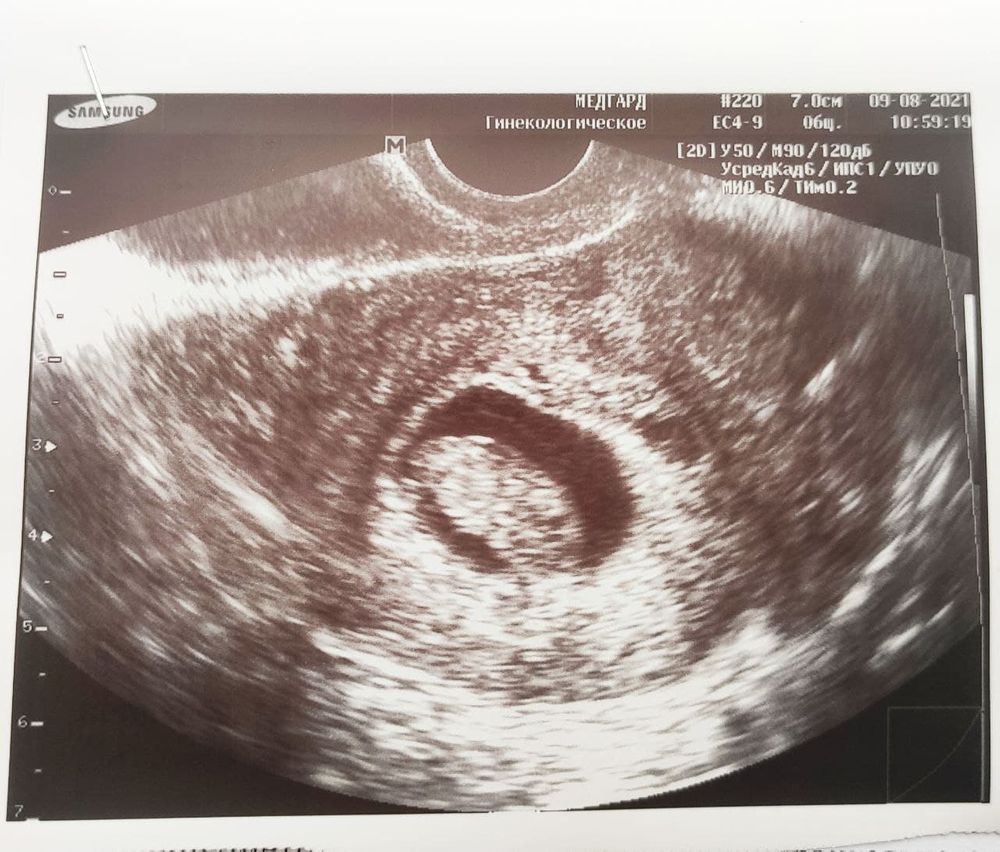

9 недель, на УЗИ всё хорошо

Но всё хорошо: КТР 21мм (9,1 нед), сердцебиение +, эмбрион двигается)

Фотка в этот раз нечеткая.